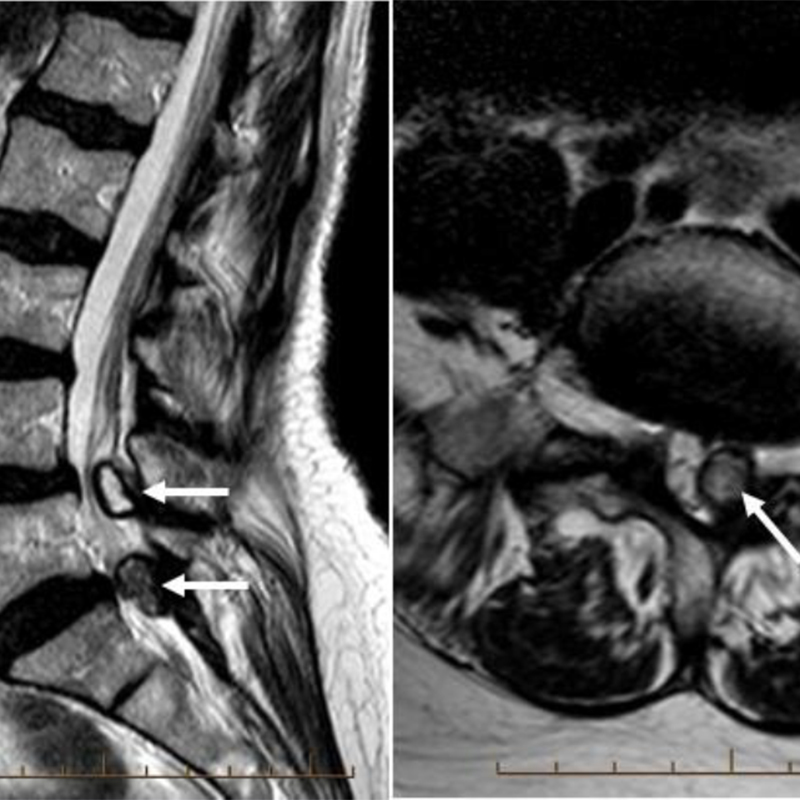

Đại cương Do những cấu trúc xung quanh của đĩa đệm cũng bị ảnh hưởng nên thuật ngữ bệnh lý thoái hóa cột sống(degenerative spine disease) thích hợp hơn thuật ngữ bệnh lý thoái hóa đĩa đệm (disc degenerative disease). Spondylosis là một thuật ngữ không đặc hiệu, nó có thể bao gồm cả bệnh lý thoái hóa cột sống. Bệnh lý thoái hóa cột sống là một quá trình […]